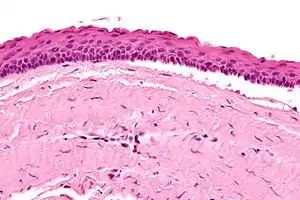

Odontogenic keratocysts have a diagnostic histological appearance. Under the microscope, OKCs vaguely resemble keratinized squamous epithelium;[14] however, they lack rete ridges and often have an artifactual separation from their basement membrane.[2]

The fibrous wall of the cyst is usually thin and uninflamed. The epithelial lining is thin with even thickness and parakeratinised with columnar cells in the basal layer which have focal reverse polarisation (nuclei are on the opposite pole of the cell).[12] The basal cells are an indication of the odontogenic origin as they resemble pre-ameloblasts. The epithelium can separate from the wall, resulting in islands of epithelium. These can go on to form 'satellite' or 'daughter' cysts, leading to an overall multilocular cyst.[9] Presence of daughter cysts is particularly seen in those with NBCCS.[12] Inflamed cysts show hyperplastic epithelium which is no longer characteristic of OKCs and can have resemblance to radicular cysts instead. Due to areas of focal inflammation, a larger biopsy is required for correct diagnosis of odontogenic keratocysts.[9]

High magnification of an odontogenic keratocyst.